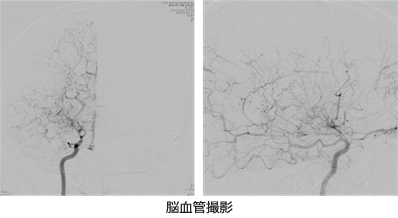

脳血管撮影では、MRAや3D-CTA以上に精密に脳血管の形態を調べることが出来ます。しかし、小児では脳虚血発作を誘発するために、検査時の渧泣を鎮静する必要や、恐怖心を除外する配慮などから麻酔が必要となるなど、侵襲的な検査となります。3D-CTA(造影CT脳血管検査)検査で、手術に必要な情報としての脳血管の様子、頭皮内の浅側頭動脈の走行を描出することは可能です。脳血管カテーテル検査に麻酔を要する場合や、脳虚血の程度が強いなど、検査の施行自体にリスクが高い場合には敢えて施行していません。手術後、病態が落ち着いて、小児期を過ぎてから、もやもや血管に認められる仮性動脈瘤の有無の検索などの必要性から、病態に応じて脳血管撮影を行うことにしています。成人では、仮性動脈瘤の頻度が高いと言われているため、その確認が必要で、手術前には必要な検査となります。